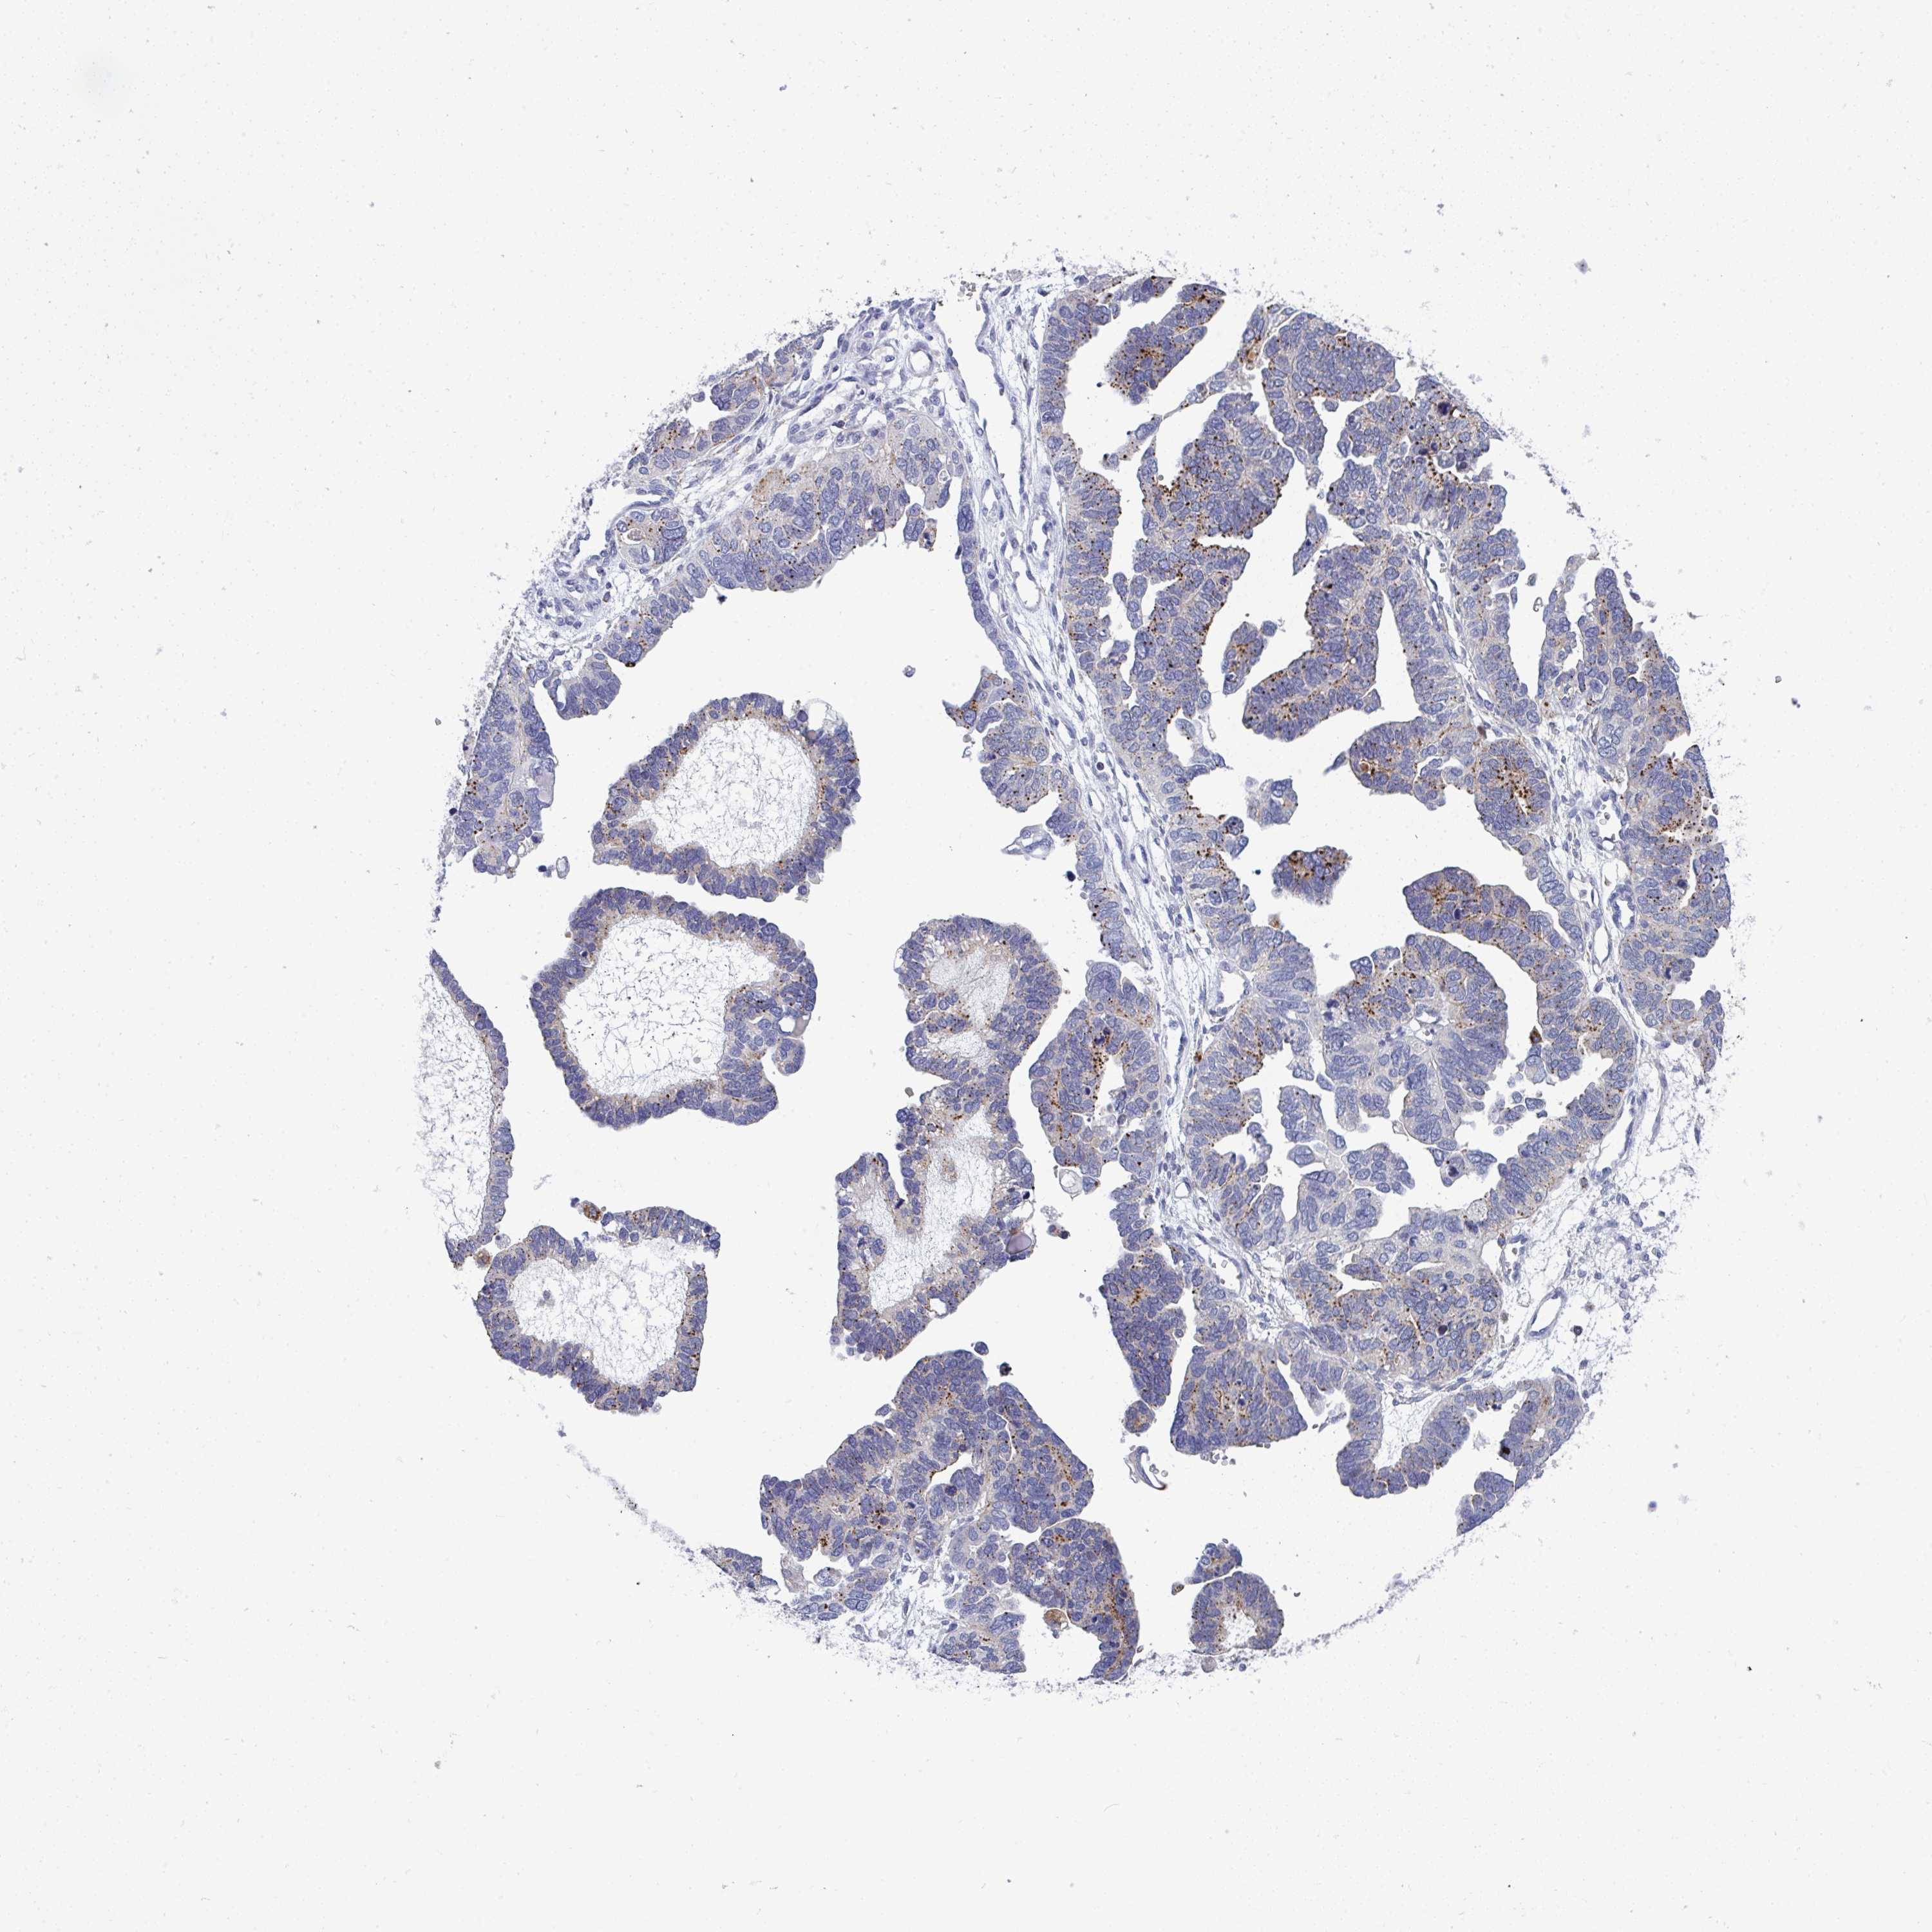

OVARIAN CANCER - Protein expressioni

A mouse-over function shows sample information and annotation data. Click on an image to view it in a full screen mode. Samples can be filtered based on level of antibody staining by selecting one or several of the following categories: high, medium, low and not detected. The assay and annotation is described here.

Note that samples used for immunohistochemistry by the Human Protein Atlas do not correspond to samples in the TCGA dataset.

Antibody stainingi

Antibody staining in the annotated cell types in the current human tissue is reported as not detected, low, medium, or high, based on conventional immunohistochemistry profiling in selected tissues. This score is based on the combination of the staining intensity and fraction of stained cells.

Each image is clickable and will lead to virtual microscopy that enables deeper exploration of all samples and also displays staining intensity scores, fraction scores and subcellular localization as well as patient and tissue information for each sample.

Antibody HPA057779

Staining

High

Medium

Low

Not detected

Intensity

Strong

Moderate

Weak

Negative

Quantity

>75%

75%-25%

<25%

None

Location

Nuclear

Cytoplasmic/membranous

Cytoplasmic/membranous,nuclear

Cystadenocarcinoma, serous, NOS

Cystadenocarcinoma, mucinous, NOS

Carcinoma, endometroid